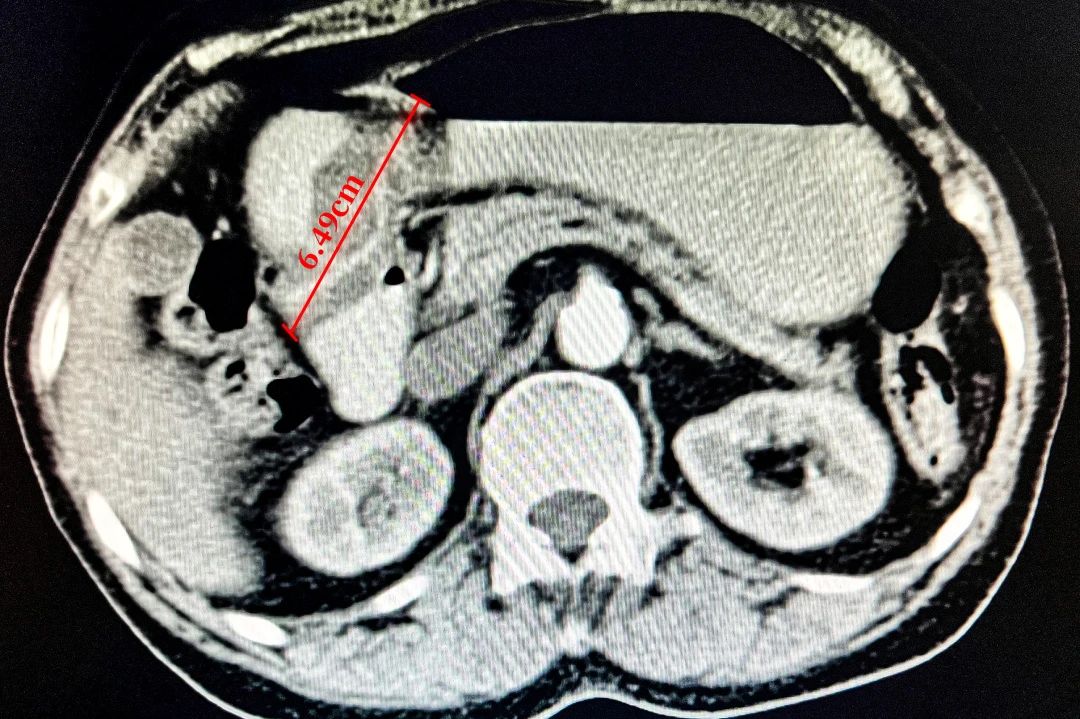

▲CT检查

消化内镜中心邓万银主任医师接诊了陈奶奶,通常大于4cm以上的肿物需要外科治疗,但细心的她发现肿物根部有个蒂部,可能是腺瘤癌变所致,且CT显示淋巴结未转移,所以如果能切除蒂部,就可以完整拿掉肿物。